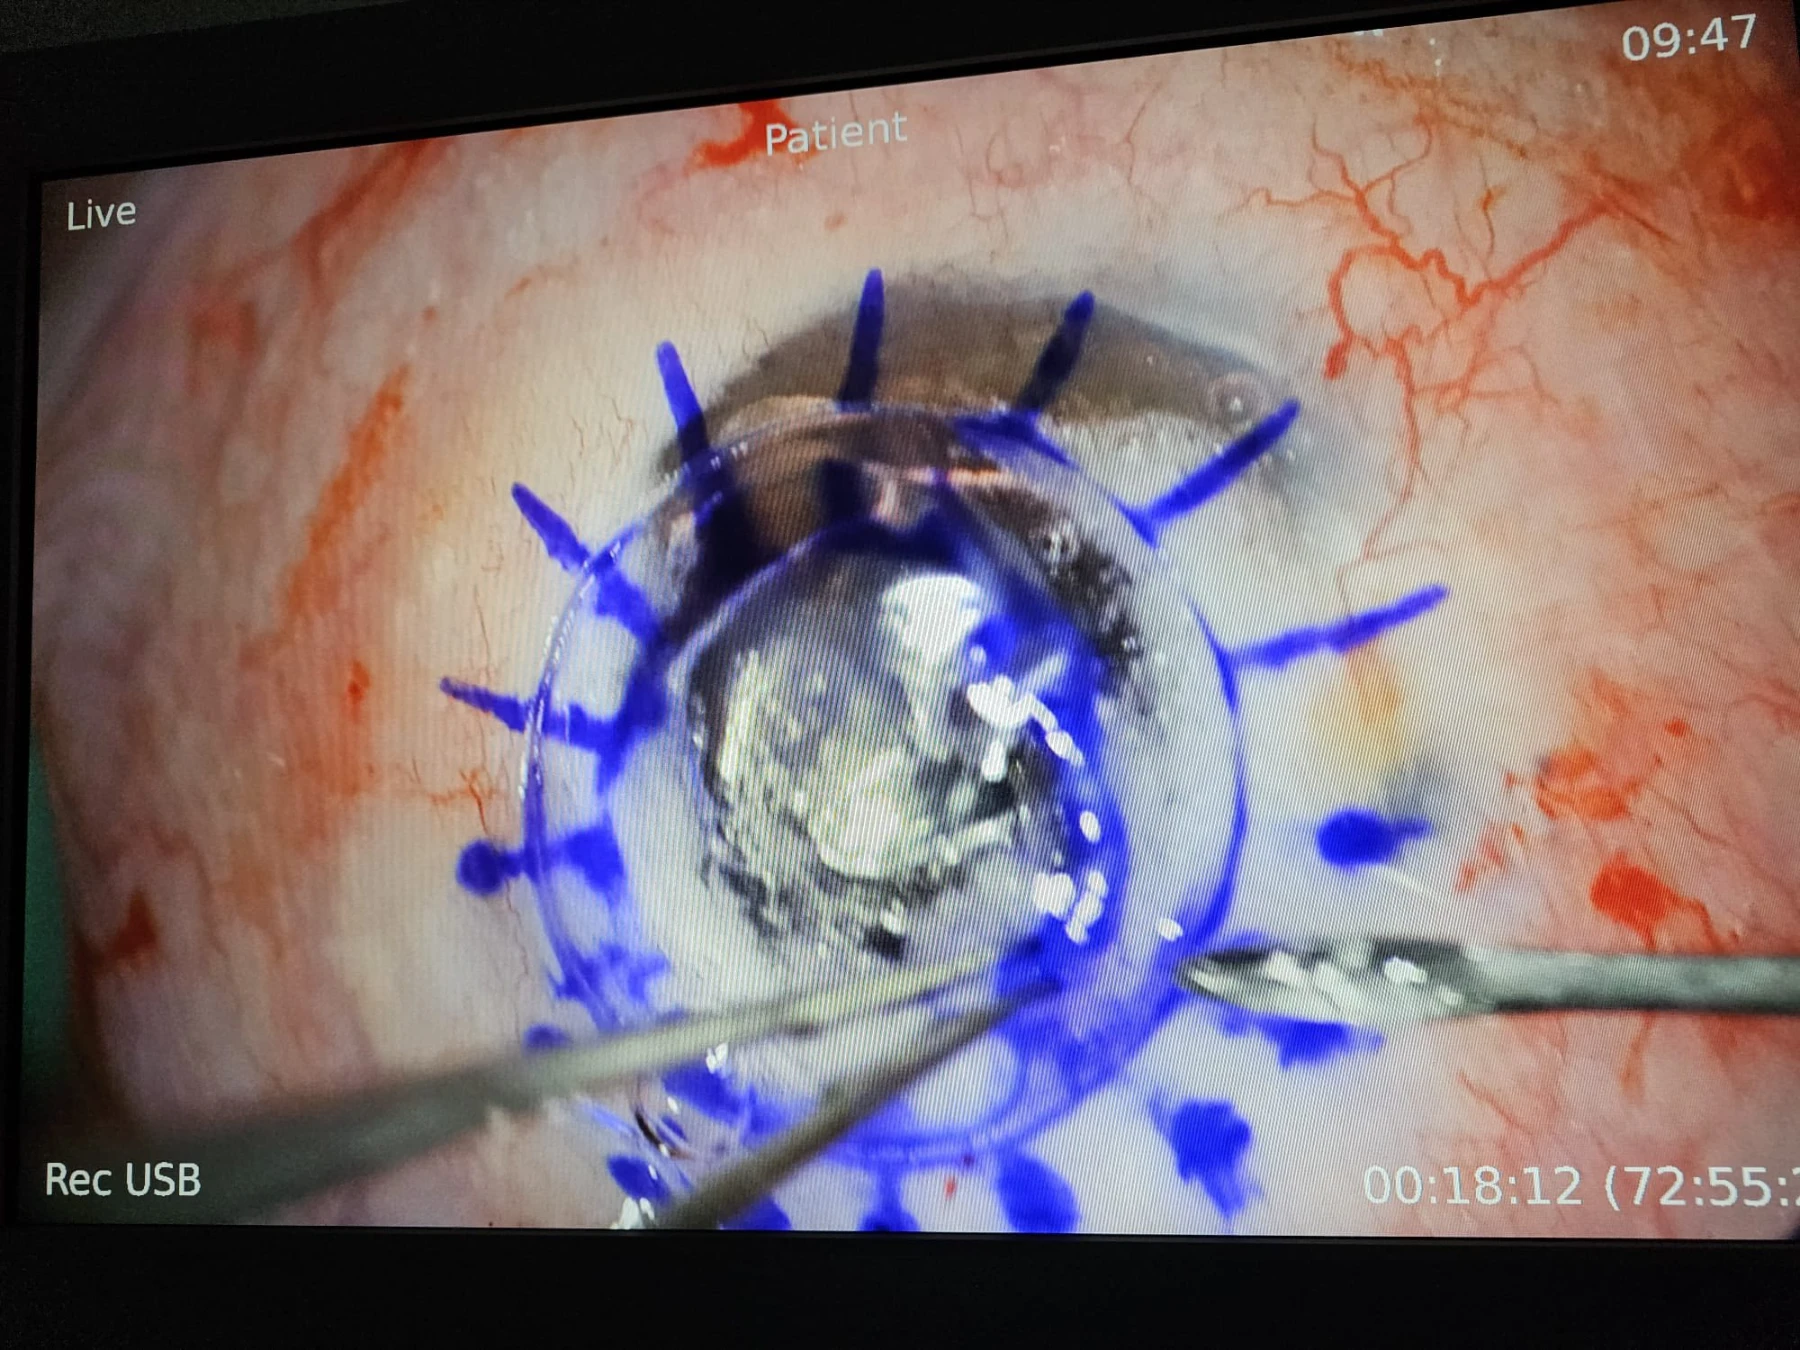

Keratoconusul este una dintre cele mai frecvent întâlnite distrofii corneene, constând în deformarea neregulată și progresivă a corneei, care ia o formă de con, cu subțiere extremă în vîrful lui, pînă la complicația de “spargere” a acestei zone foarte subțiate, urmată de hidrops cu perforație sau / și de cicatrici fibroase în vârful acestui con. În stadiile lui cele mai avansate, când vederea pacientului este foarte scăzută, singurul tratament este operația de transplant de cornee, iar tehnica de elecție este transplantul lamelar anterior DALK, deoarece, prin acesta, se păstrează endoteliul cornean propriu al pacientului, endoteliul fiind stratul cel mai “valoros” al corneei, dar și cel răspunzător pentru 90% din situațiile de respingere a grefonului – de aceea, dacă se poate păstra, merită păstrat!

Iar când pacientul este foarte tânăr (17 ani în cazul de azi) și boala e avansată la ambii ochi, tânărul neputând să se descurce singur, nu doar că operația se impune cât mai repede, dar e de dorit să fie un transplant lamelar anterior DALK sau unul perforant “Mushroom”, cu păstrarea unei suprafețe cât mai mari din endoteliul propriu pacientului.

Tehnologia femtolaser este de mare folos în ambele tehnici menționate. Mai jos, cîteva secvențe din operația efectuată de dr. Cristian Moraru.